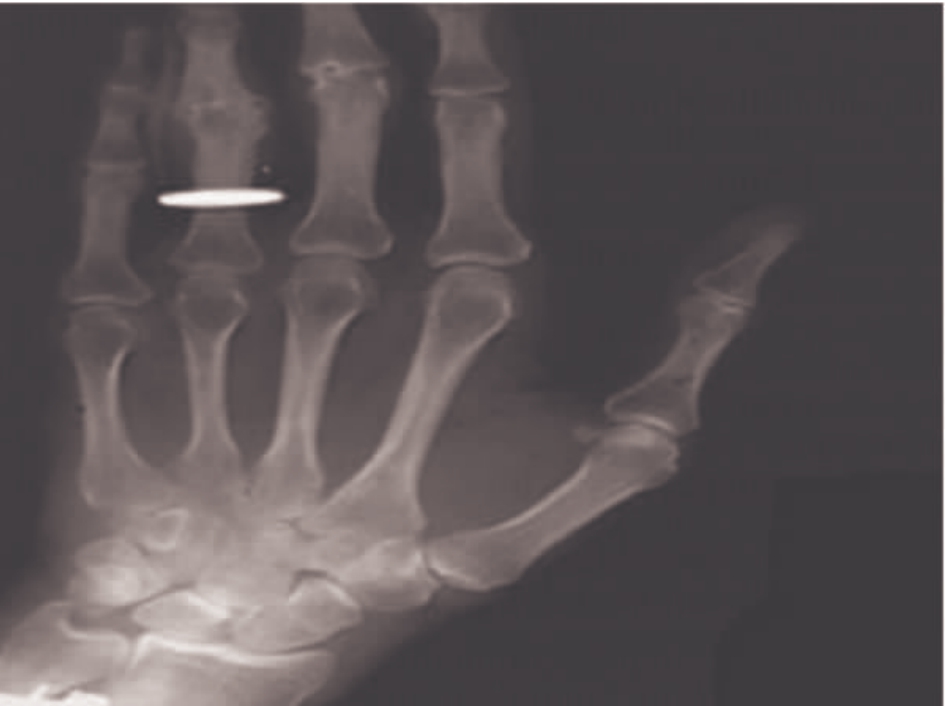

从广义上说,图像是自然界景物的客观反映,是人类认识世界和人类本身的重要源泉。照片、绘画、影视画面无疑属于图像;照相机、显微镜或望远镜的取景器上的光学成像也是图像。1826年世界上出现了第一张照片《窗外》(见图1-1),1895年德国物理学家伦琴教授发现了世界上第一张X光图像(见图1-2),由于他的发现,他获得了1901年诺贝尔物理学奖。这些具有历史意义的图像,在人类文化传播领域和医学领域发挥了巨大的作用,同时也促进了图像技术的发展。

img3

图1-2 世界上第一张X光图像